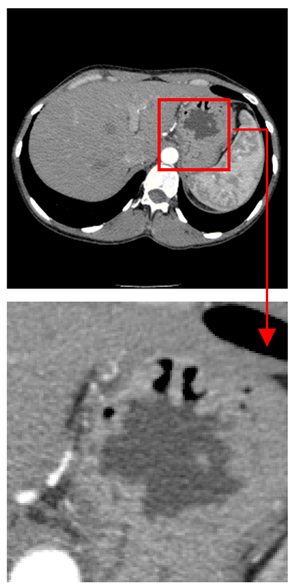

| Original Medical Images | |||||||

| Pair 1 | Pair 2 | Pair 3 | Pair 4 | ||||

![]() (1-9) PSNR = 44.14 | ![]() (1-10) PSNR = 41.90 | ![]() (1-11) PSNR = 40.09 | ![]() (1-12) PSNR = 41.41 | ![]() (1-13) PSNR = 42.24 | ![]() (1-14) PSNR = 40.35 | ![]() (1-15) PSNR = 40.79 | ![]() (1-16) PSNR = 40.84 |

| Shadow Images Produced by Using LSBs | |||||||

![]() (1-17) PSNR = 26.35 | ![]() (1-18) PSNR = 25.49 | ![]() (1-19) PSNR = 23.57 | ![]() (1-20) PSNR = 24.19 | ![]() (1-21) PSNR = 24.79 | ![]() (1-22) PSNR = 24.23 | ![]() (1-23) PSNR = 23.26 | ![]() (1-24) PSNR = 24.42 |

| Shadow Images Produced by Using Middle Bits | |||||||

![]() (1-25) PSNR = 18.97 | ![]() (1-26) PSNR = 19.95 | ![]() (1-27) PSNR = 14.10 | ![]() (1-28) PSNR = 13.84 | ![]() (1-29) PSNR = 16.66 | ![]() (1-30) PSNR = 13.23 | ![]() (1-31) PSNR = 13.38 | ![]() (1-32) PSNR = 14.75 |

| Shadow Images Produced by Using MSBs | |||||||